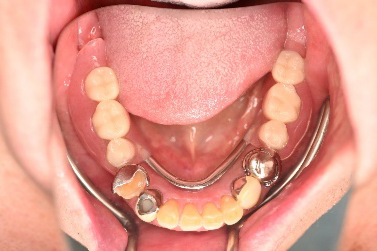

Before

※赤丸を抜歯しました。

After